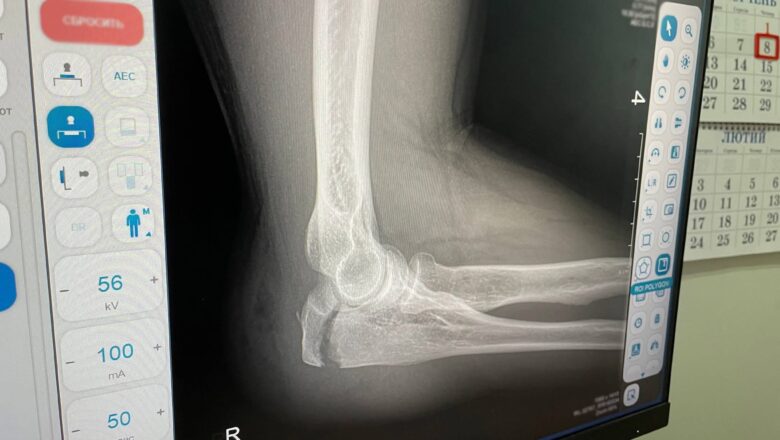

За словами лікарів-ортопедів-травматологів КНП НМР «СМСЧ м. Нетішин», найпоширенішими наслідками падінь є розтягнення зв’язок, вивихи та забої м’яких тканин. На перший погляд, такі ушкодження можуть здаватися несерйозними — «переболить», «розходиться». Проте медики застерігають: більшість ускладнень виникає саме через зволікання.

Набряк, посилення болю, обмеження рухів, приховані мікротріщини або пошкодження зв’язок можуть проявитися не одразу, а за кілька годин або навіть днів після падіння. Саме тому своєчасне звернення до травмпункту — не пересторога, а необхідність.